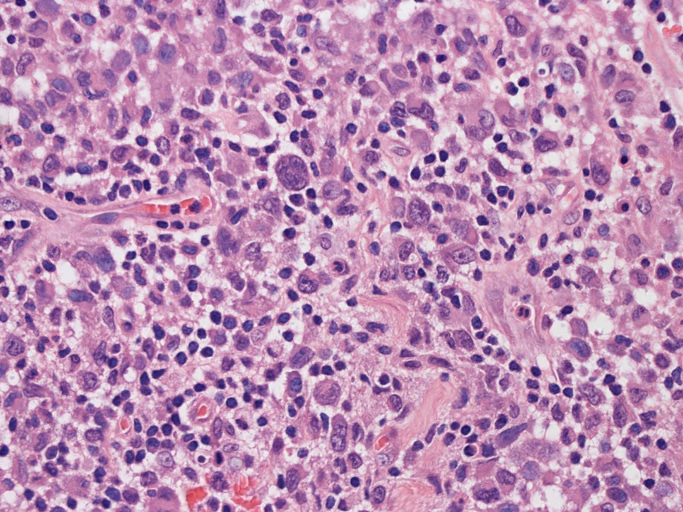

大型細胞の増殖よりなる腫瘍。縦溝,しわ,切れ込みのある核をもった大型細胞も出現する。クロマチンは顆粒状で核小体も明瞭である。核分裂は >50/10hpfと多い。eosinophilsは少ない。壊死が多発することがある。未分化ないし低分化な細胞像, 組織所見のため鑑別診断は多岐にわたり、的確な免疫染色を行う必要がある。

皮膚に異型細胞の浸潤がみられる。異型細胞は表皮内に浸潤するほか、表皮真皮境界部, 真皮, 皮下脂肪組織にもびまん, 結節様の浸潤所見を示す。血管周囲に浸潤、集蔟する所見も多く見られる。 増殖浸潤細胞の核には類円形や腎臓形, またはへこみ, 切れ込み, 溝などを有する多型な核が認められる。クロマチンは粗でvesicularな核が多い。核小体の明らかな核もある。好エオジン性の核内封入体様構造も少数に見られた。mitosisは容易に認められる。hyperchromaticな多型核, bizzarreな細胞が高頻度に認められ異型度は高いと考えられる。細胞質は境界不明瞭, 淡明または泡沫様の 好エオジン性胞体である。